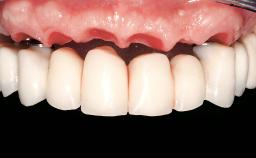

Immediate Loading of Six Implants in the Mandible and Six Implants in the Maxilla and Final Restoration with Full-Arch CAD/CAM Metal Framework FDPs Involving Digital Planning and Guided Surgery

Immediate loading of dental implants is increasingly popular with clinicians and patients. The idea of delivering a restoration directly after implant insertion,combined with a less invasive procedure (flapless protocol), has made treatment protocols involving dental implants more accessible to dentists and patients. However,immediate-loading concepts require sophisticated and exact planning. To facilitate this, conventional panoramic tomographs and periapical radiographs are often taken with the patient wearing a radiographic template simulating the preoperative prosthetic design. However, these radiographs do not provide all the necessary information. In addition, some protocols call for conventional surgical templates fabricated on the diagnostic cast. These will inform the bone drilling points and drill angles, but do not reference the underlying anatomical structures or provide exact 3-D guidance.

Defining Characteristics Fully edentulous upper jaw to be rehabilitated with an implant-borne fixed dental prosthesis

Loading Protocol Immediate

Retention Screw-retained, with 4 or more splinted implants Screw-retained, with 4 or more splinted implants